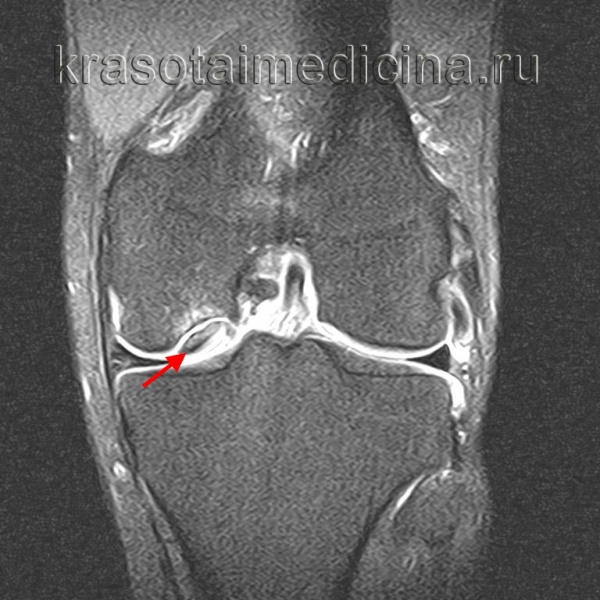

5. Артроскопия:

- Артроскопия локтевого сустава обеспечивает непосредственную визуализацию поражения при РОХ, а также позволяет осмотреть головку лучевой кости и все остальные участки суставной поверхности. Также этот метод позволяет оценить стабильность фрагмента (рис. 2) и выполнить необходимые лечебные манипуляции